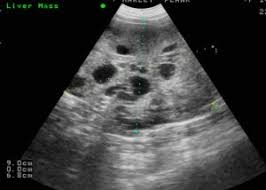

Signs Of Liver Cancer In Dog / Signs Of Cancer In Dogs Cats Vetdepot Com : Diagnosing liver cancer in dogs.. Some of the signs of liver cancer that you may notice are excessive vomiting, reduced appetite, pale gums, distended stomach, jaundice or breathing disorders. Do not wait for your. Liver disease problems in dogs treatment & homemade recipe. No one knows exactly why melanomas develop, although genetic factors seem to play a role. Webmd discusses the signs of skin cancer in dogs and which breeds are more likely to get skin cancer.

Dogs can develop primary liver cancer, or metastatic (secondary) liver cancer. Cancer is very common in pets just like it is in people. No one knows exactly why melanomas develop, although genetic factors seem to play a role. What are the signs of cancer in dogs? Symptoms of liver cancer in dogs.

12 Diet For Liver Shunt In Lucy Ideas Dog Food Recipes Dog Recipes Healthy Dog Food Recipes from i.pinimg.com Liver disease problems in dogs treatment & homemade recipe. Large tumors can still be a problem if they rupture and bleed, or if they put pressure on other abdominal organs. Your dog might attempt to swallow small pieces of the pork bone, which could lead to choking, intestinal blockages, or damage to the esophagus or intestines. If your dog is getting older. Liver cancer happens when liver cells develop changes (mutations) in their dna. Some of the signs of liver cancer that you may notice are excessive vomiting, reduced appetite, pale gums, distended stomach, jaundice or breathing disorders. Early diagnosis of cancer will help combat the disease effectively and greatly improve the prognosis. Malignant liver tumors have been reported to metastasize to other organs such as regional lymph nodes, lungs.

Cancers often spread to the liver with metastasis, but primary liver cancer is rare in dogs.

You might notice this as the dog taking a. Large tumors can still be a problem if they rupture and bleed, or if they put pressure on other abdominal organs. Your vet may run lab tests to look for signs of liver dysfunction such as a urine sample test to diagnose liver cancer. Indeed, 1 in 4 dogs dies of cancer every year. Seizures are possible signs of a wide range of diseases including liver disease, toxins, or brain tumor. Webmd discusses the signs of skin cancer in dogs and which breeds are more likely to get skin cancer. This type of liver cancer in dogs originates in other organs or parts of the body, and may affect the liver as a secondary location. The clinical signs of stage 4 liver cancer in dogs are as following the veterinarian will examine your dog's abdomen to feel if there is fluid accumulation and check the skin for. What are the signs of cancer in dogs? How to cancer start, signs of skin cancer, how to cancer come so stay tuned and subscribe. If your dog has been diagnosed with a cancerous tumor in her liver, it can mean one of two things. It's important to remember that these symptoms could also be caused by other health conditions. It is most often found in the spleen, liver, and.

A cell's dna is the material that provides instructions for every chemical process in your body. Tumors that develop within the liver may be either benign (noncancerous) or malignant (cancerous). Malignant liver tumors have been reported to metastasize to other organs such as regional lymph nodes, lungs. No one knows exactly why melanomas develop, although genetic factors seem to play a role. It is most often found in the spleen, liver, and.

How To Spot The Early Signs Of Liver Disease In Dogs Dogs Naturally from www.dogsnaturallymagazine.com How to cancer start, signs of skin cancer, how to cancer come so stay tuned and subscribe. Generalized illnesses, signs of jaundice. Indeed, 1 in 4 dogs dies of cancer every year. Cancer is very common in pets just like it is in people. Liver cancer in dogs is fairly uncommon, with pet cancer center estimating that this type of cancer makes up only 1.5 percent of all the most common signs include a decreased appetite, vomiting, weight loss, weakness and lethargy. Diagnosing liver cancer in dogs. Cancers often spread to the liver with metastasis, but primary liver cancer is rare in dogs. Their powerful noses can also detect viruses, bacteria, and signs of cancer in a person's body or bodily fluids.

Cancer is defined as uncontrolled growth of abnormal cells, but cancer is a very complex and complicated disease. They tend to grow extremely fast and are likely to spread to other organs, including the lungs and liver. Your vet may run lab tests to look for signs of liver dysfunction such as a urine sample test to diagnose liver cancer. Tumors can start in the liver, or spread to the liver from another cancer in the body. The causes of cancers are largely unknown, making prevention difficult. As human cancer deaths rise in the united states another type of cancer that often has no obvious clinical signs is hemangiosarcoma. However, having said this it is more common for ragwort which is notoriously bad for horses is also very bad for dogs. Cancer in dogs is just one cause of weight loss. Liver disease problems in dogs treatment & homemade recipe. Being aware of possible signs of cancer in pets helps provide early. Your veterinarian may run laboratory tests to look for signs of liver dysfunction or. Malignant liver tumors have been reported to metastasize to other organs such as regional lymph nodes, lungs. Diagnosing liver cancer in dogs.

How to cancer start, signs of skin cancer, how to cancer come so stay tuned and subscribe. Cancer is a word that strikes fear in the hearts of dog owners. Symptoms of liver cancer in dogs decreased appetite. A dog with liver cancer may become disinterested in food, not finishing its usual portion or even refusing to eat at all. Are you worried that your dog might have cancer? A dog may show a high interest in drinking large amounts of. The symptoms of liver cancer in dogs and cats usually indicate the prevalence. They tend to grow extremely fast and are likely to spread to other organs, including the lungs and liver. You might notice this as the dog taking a. Owners need to be alert to signs of this on the other hand, another dog with a different type of liver cancer could be extremely sick, have tumors throughout his body early in the course of the. Just remember that many conditions, not just cancer, can cause similar clinical signs, and that the. Here are some of the most common symptoms of cancer in dogs. Two types of liver cancer in dogs.